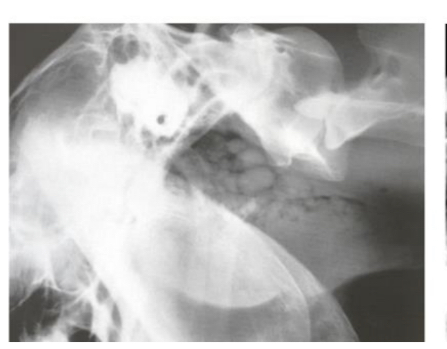

Q

This is a latero-lateral view of the head. What abnormal findings are highlighted?

A

Visible fluid line within the guttural pouch

This is due to the presence of pus in the guttural pouch